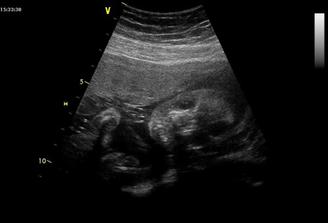

Panu doktorovi se nelíbily mozkové komory našeho broučka, že jsou moc velké, tak si nás pozval k Apolináři hned na druhý den. Tak to konzultoval ještě s kolegou, kterému se to taky nezdálo a ani nenašli část mozku- spojnici mezi dvěma hemisférami....proto hned mažeme na magnetickou rezonanci...40 minut si s Tobíkem "užíváme" tunelu a doufáme, že vše bude OK...ale bohužel dobré zprávy nepřišly...MR nezobrazila to, co by měla...jsme poslaní na genetiku, já brečím jak želva a jsem v šoku. Paní doktorka je moc milá, snaží se nám vše vysvětlit, ale její verdikt, že je to tak 50/50 - zdravé/postižené dítě mne děsí...vždyť je to 1:1!!!!! Po domluvě a doporučení se objednáváme na AMC, v lepším případě na odběr pupečníkové krve....

15.10.- další kontrolní UZUZ nedopadl moc dobře, komory se zvětšily na 16 mm...bohužel doktoři nedokážou nic víc k tomu říct...jen že to není dobré, ale ještě není nic ztraceno...další UZ 5.11.- Tak zas pár milimetrů nárůst (na 19 mm)...co to přinese? Bůh ví...další UZ 26.11....pak už asi kontroly v porodnici, kde budu rodit - v Motole. Komory si rostou dále jak chtějí, i když nám se to vůbec nelíbí...22,5 mm.

5.12.- konziliární UZ v Motole....zas výsledky horší....komory 27 mm!!!! Podle doktora je jasná oboustranná totální ageneze corpus callosum, 4. mozková komora hraniční stav, to zvětšení už je hydrocefalus a mírně již zvětšuje mimču hlavičku.....Porod by chtěl doktor uspíšit, aby hlavička ještě víc nenarostla, takže před Vánoci....Myslela jsem, že už mne nic nerozhodí, ale rozhodilo...rozbrečela jsem se tam normálka natvrdo, nějak mi docházej síly a optimismus. Nevím, jak to zvládnem...